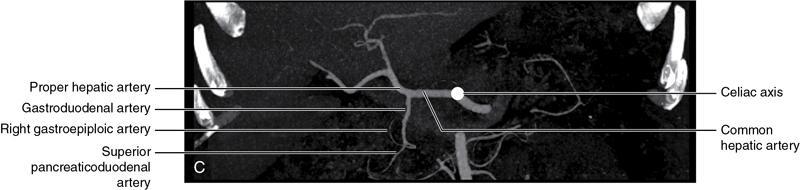

CROSS SECTIONAL ANATOMY OF ABDOMEN Satya Jha NORMAL ANATOMY OF ABDOMEN AND PELVIS Amandeep Singh The two major surfaces: The anterior and posterior layers of the coronary ligament converge on bare area (not covered by peritoneum). Its right and left margins form the right and left triangular ligaments. The right triangular ligament extends toward the diaphragm and separates right subphrenic space from right subhepatic space. The left triangular ligament gives tracts extending to the diaphragm and falciform ligament and does not compartmentalize the left subphrenic space. Ligamentum teres or the obliterated umblical vein is contained in falciform ligament which attaches the liver to anterior abdominal wall. The main portal vein, the proper hepatic artery and the common bile duct are contained within investing peritoneal folds of hepatoduodenal ligament at the porta hepatis (Fig. 7.2.2.1). Liver is divided into eight segments which are functionally independent and have their own vascular supply and biliary drainage. Arterial circulation: The branches of the hepatic artery accompanying the portal veins. Hepatic venous system: The right, middle, and left hepatic veins draining into IVC (Figs. 7.2.2.2 and 7.2.2.3). The gallbladder is a blind pear-shaped muscular membranous sac which is an embryologic derivative of the foregut, is a pouch lying along the undersurface of the liver. The gallbladder fossa is located in the plane of the interlobar fissure, which lies between the right and left hepatic lobes. Its major function is to store and concentrate bile which is produced by the liver. It measures approximately 4 cm in diameter when it is normally distended. Gallbladder is a smaller tubular structure in contracted state. The normal gallbladder wall thickness ranges from 1 to 3 mm. The gallbladder is divided into the fundus, body and neck. Infundibulum is present in the region of neck of the gallbladder, which is called the Hartmann pouch, where gallstones are usually impacted. Intrahepatic biliary radicles (IHBRs) scattered throughout the liver get confluent towards the hilum. They unite to form the right and left main hepatic ducts which further unite to form common hepatic duct (CHD) at the hilum. Common bile duct is formed by the union of cystic duct with common hepatic duct. The main pancreatic duct is joined with the common bile duct to form the ampulla of Vater at the major duodenal papilla (Figs. 7.2.2.4 and 7.2.2.5). Pancreas is located in anterior pararenal space of retroperitoneum anterior to perirenal (Gerota’s) fascia and posterior to parietal peritoneum. It is divided into head, uncinate process, neck, body and tail from right to left. Pancreas lies anterior to portal vein, which marks the point of transition between the body and neck. The region between head of pancreas and second and third parts of duodenum is known as the pancreatic groove. In postnephrectomy cases or with agenesis of kidney or ectopic kidney, pancreas moves posteriorly to partially fill in the empty renal fossa; its soft tissue density should not be mistaken for recurrent tumour. It is located in the pancreatic groove and is bounded superiorly by the duodenal bulb, laterally by second portion of duodenum, inferiorly by third portion of duodenum, medially by superior mesenteric vein and anterior to inferior vena cava. It is a wedge or wedge shaped lying posterior to superior mesenteric artery and vein. It is an imaginary junction between the head and body and lies directly over the junction of the splenic vein and superior mesenteric vein. It is located posterior to the lesser sac and anterior to the aorta, left adrenal gland, left kidney, and renal vessels and runs obliquely upward to the left of the superior mesenteric vessels. It is situated median to the colonic flexure and anterior to the left kidney. It is located in close proximity to the splenic hilum without a notable relation with the body of pancreas. It is seen anterior to the left kidney and median to the colonic flexure. The distal part of the tail passes between the peritoneal layers of the splenorenal ligament (Fig. 7.2.2.6 and 7.2.2.7).